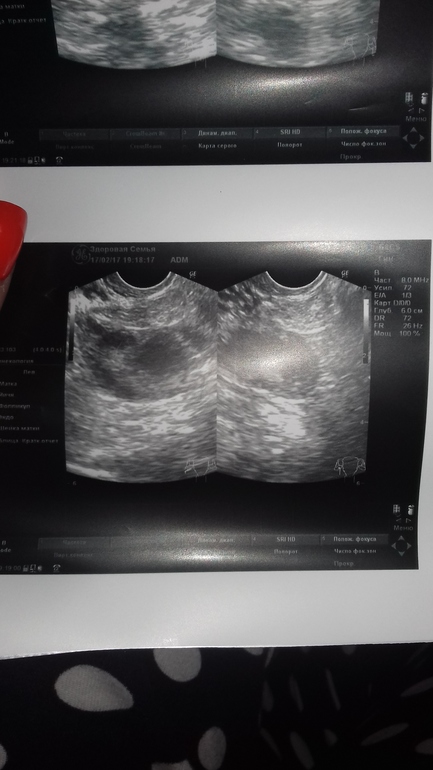

персистенция желтого тела?!

На УЗИ такой диагноз поставил, все нормально, ни кист ничего, матка чуть чуть увеличена.

У меня после протокола все никак не могут наладиться, месячные мазня 1-2 дня, но по графику) это на 5 д.ц узи...я просто думаю может у кого было, у меня первый раз такие снимки узи, пятна прям какие то, непонятные